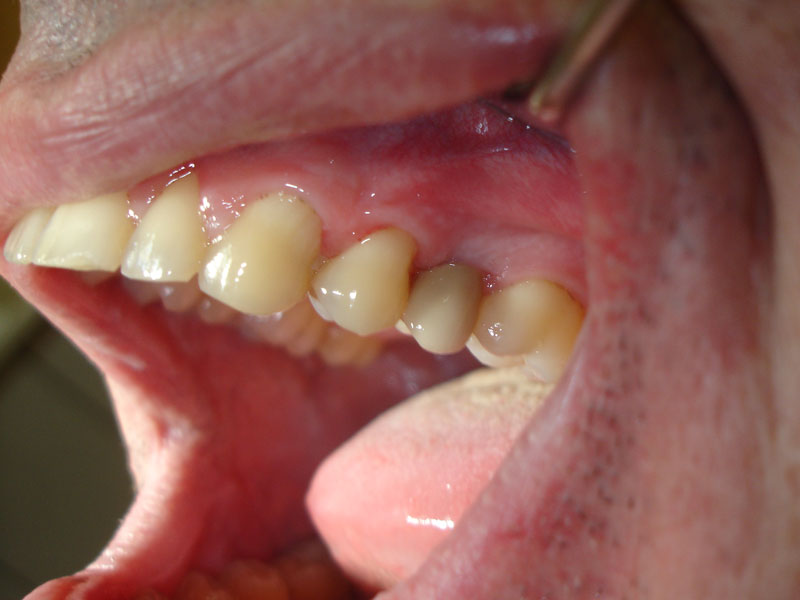

Folosim implanturi dentare WhiteSky si BlueSky, produse de firma Bredent, in Germania.

Prin tratamentul cu implanturi dentare se asigura refacerea arcadelor dentare atunci cand nu se doreste devitalizarea si slefuirea unor dinti, sau atunci cand nu sunt suficienti dinti pe care sa poata fi realizata o restaurare protetica fixa.

Implanturile dentare pot fi realizate din titan sau, mai nou, din zirconiu. Implanturile dentare din titan sunt implanturi folosite foarte des si care si-au dovedit rezistenta in timp.

Implanturile dentare de zirconiu sunt mai nou aparute, prezinta o biocompatibilitate si o estetica superiora celor din titan. Sunt indicate in special in zona frontala.